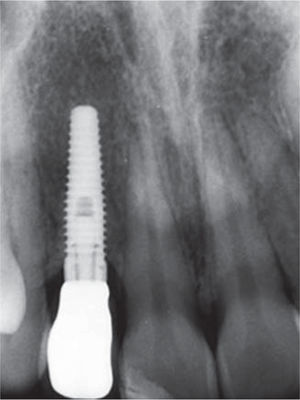

A la valoración radiográfica se aprecia un diente con tratamiento endodóntico, una lesión en el periápice y un poste de fibra de vidrio (Figura 2).